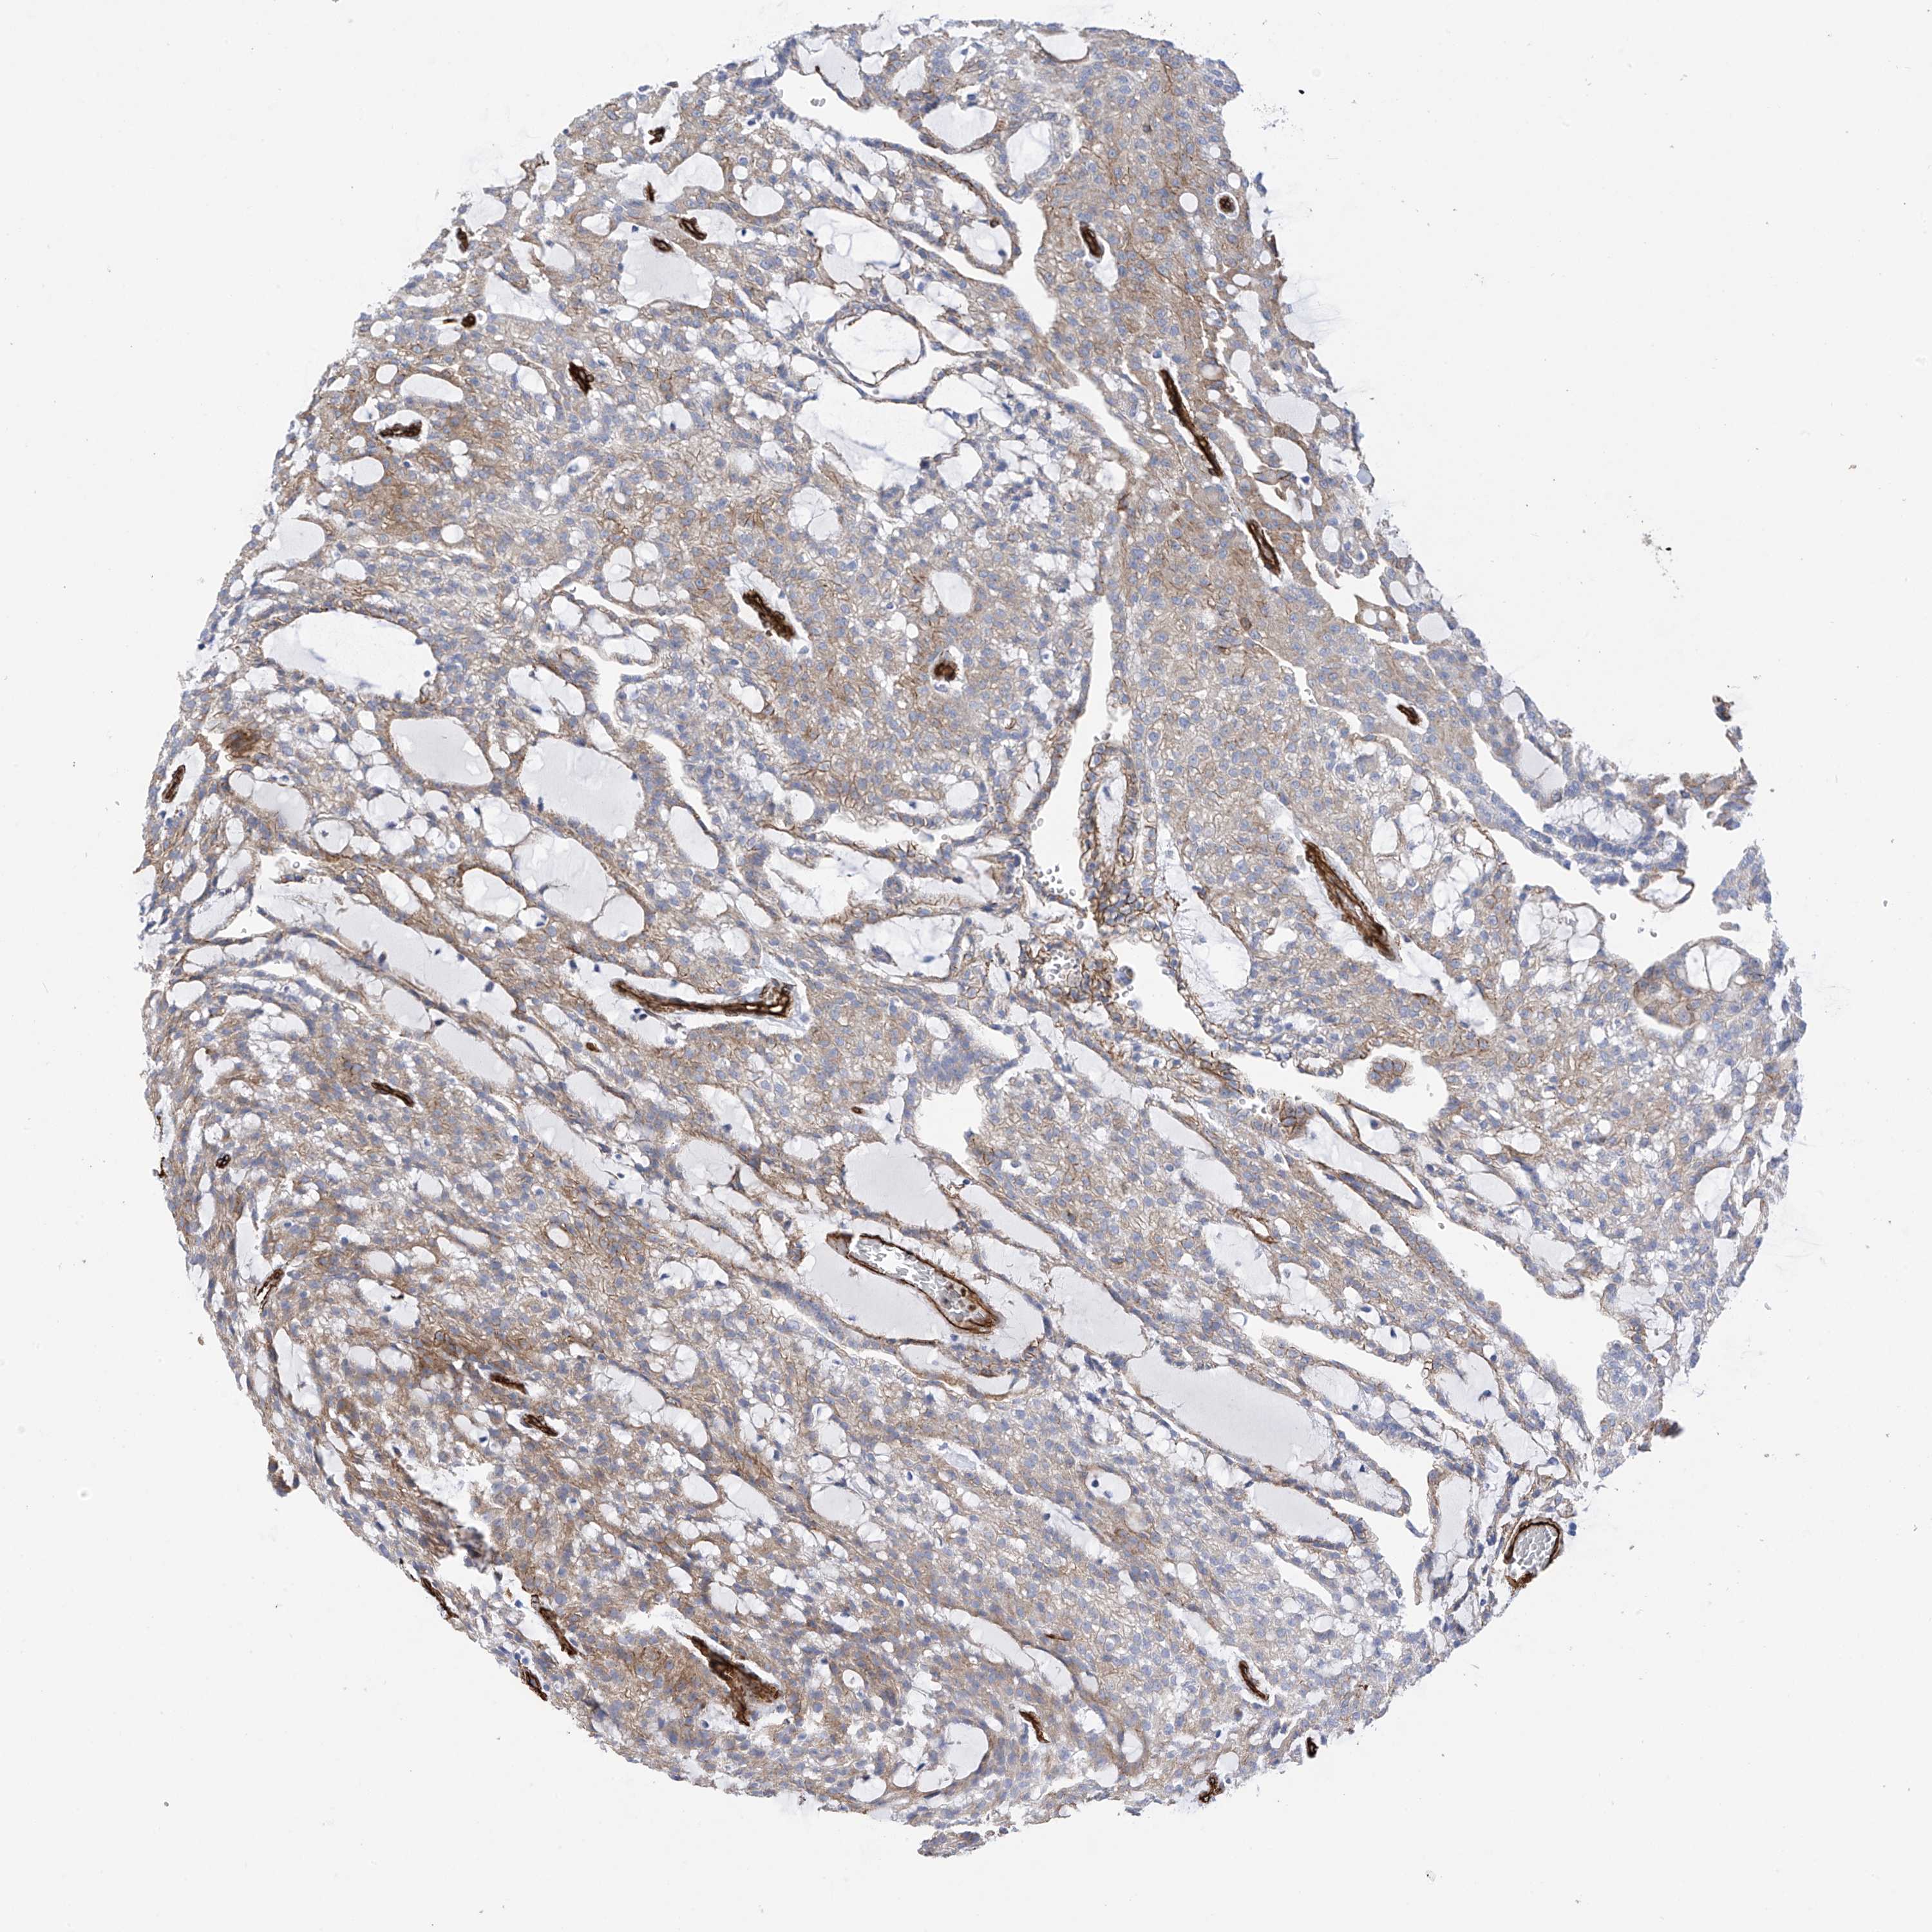

KIDNEY RENAL CLEAR CELL CARCINOMA (VALIDATION) - Interactive survival scatter ploti

The Survival Scatter plot shows the clinical status (i.e. dead or alive) for all individuals in the patient cohort, based on the same data that underlies the corresponding Kaplan-Meier plots. Patients that are alive at last time for follow-up are shown in blue and patients who have died during the study are shown in red.

The x-axis shows the expression levels (FPKM) of the investigated gene in the tumor tissue at the time of diagnosis. The y-axis shows the follow-up time after diagnosis (years). Both axes are complimented with kernel density curves demonstrating the data density over the axes. The top density plot shows the expression levels (FPKM) distribution among dead (red) and alive patients (blue). The right density plot shows the data density of the survived years of dead patients with high and low expression levels respectively, stratified using the cutoff indicated by the vertical dashed line through the Survival Scatter plot. This cutoff is automatically defined based on the FPKM cutoff that minimizes the p-score. The cutoff can be changed by dragging the vertical line or by entering a cutoff value in the square labeled "Current cut-off".

Under the Survival Scatter plot the p-score landscape (black curve; left axis) is shown together with dead median separation (red curve; right axis). Dead median separation is the difference in median mRNA expression between patients who have died with high and low expression, respectively. It is calculated as follows: median FPKM expression of dead patients with high expression - median FPKM expression of dead patients with low expression. This is intended to aid the user in visually exploring custom cutoffs and the associated p-scores and dead median separation.

Individual patient data is displayed and can be filtered by clicking on one or more of the category buttons on the top of the page. Categories describing expression level and patient information include: high, low, alive, dead, female, male and tumor stages. The scale of the x-axis can be toggled between linear and log-scale by clicking on the "x log" button. Mouse-over function shows TCGA ID, patient information and mRNA expression (FPKM) for each patient.

& Survival analysisi

Kaplan-Meier plots summarize results from analysis of correlation between mRNA expression level and patient survival. Patients were divided based on level of expression into one of the two groups "low" (under cut off) or "high" (over cut off). X-axis shows time for survival (years) and y-axis shows the probability of survival, where 1.0 corresponds to 100 percent.

UBTD1 is not prognostic in Kidney Renal Clear Cell Carcinoma (validation)

Best expression cut offi

Based on the FPKM value of each gene, patients were classified into two groups and association between prognosis (survival) and gene expression (FPKM) was examined. The best expression cut-off refers the FPKM value that yields maximal difference with regard to survival between the two groups at the lowest log-rank P-value. Best expression cut-off was selected based on survival analysis .

When clicking on this number, the vertical dashed line indicating cut-off, the interactive survival plot, and the Kaplan-Meier curve will be adjusted to show results based on the best expression cut-off.

: 16.35

Median expressioni

Median expression refers to the median FPKM value calculated based on the gene expression (FPKM) data from all patients in this dataset. When clicking on this number, the vertical dashed line indicating cut-off, the interactive survival plot, and the Kaplan-Meier curve will be adjusted to show results based on the median expression.

: N/A

Median follow up timei

Median follow up time refers to the median time (years) after diagnosis with this type of cancer, based on clinical data from all patients in this dataset.

P scorei

Log-rank P value for Kaplan-Meier plot showing results from analysis of correlation between mRNA expression level and patient survival.

N/A

5-year survival highi

5-year survival for patients with higher expression than the expression cutoff.

For melanoma and glioma, 3-year survival is shown.

5-year survival lowi

5-year survival for patients with lower expression than the expression cutoff.

TCGA RNA samplesi

RNA-seq data is reported as average FPKM (number Fragments Per Kilobase of exon per Million reads), generated by the The Cancer Genome Atlas (TCGA) .

Normal distribution across the dataset is visualized with box plots, shown as median and 25th and 75th percentiles. Points are displayed as outliers if they are above or below 1.5 times the interquartile range. FPKM values of the individual samples are presented next to the box plot.

Average pTPM 13.8

Number of samples 100